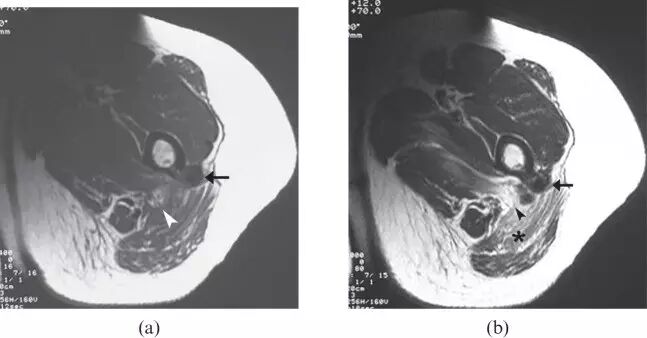

![]()

图25.一个67岁的男性结节型肌肉结节病,左大腿软组织包块,伴随腿疼痛。 (a)轴向T1加权磁共振图像显示在左腿的腓肠肌和胫骨前肌中的低信号强度结节(箭头)。 (b)轴向T2加权的MR图像显示由高信号强度(箭头)的厚边缘包围的中心低信号强度的肌内小腿损伤(箭头)。 ,在四头肌(箭头)中具有急剧的边缘状增强。 活检揭示非梗阻性肉芽肿。 T,胫骨。